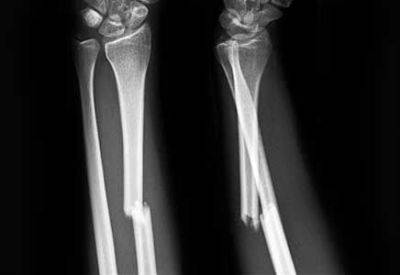

Перелом длинных трубчатых костей

Перелом — нарушение целости кости под действием травмирующей силы. Наиболее часто происходят переломы длинных трубчатых костей — бедренной кости, плечевой кости, костей предплечья и костей голени. Переломы длинных трубчатых костей по локализации делят на диафизарные, метафизарные и эпифизарные. Патофизиология

При переломах трубчатых костей часто отмечаются следующие виды смещений отломков: 1) боковое, или по ширине; 2) продольное с захождением и расхождением отломков; 3) угловое, или по оси; 4) ротация отломков вокруг продольной оси конечности. Обычпо смещение отломков происходит одновременно в нескольких плоскостях и направлениях. При смещении отломков возможно ущемление между ними мышц, сосудов, нервов (интерпозиция тканей). Переломы могут сопровождаться взаимным смещением суставных поверхностей — вывихами или подвывихами. Эти переломы относятся к группе переломовывихов.

У детей травматические переломы имеют свои особенности. Перелом, как правило, носит изолированный характер. Перелом верхних конечностей наблюдается в два раза чаще, чем нижних. Наблюдаются также травматические эпифизиолизы и апофизиолизы, например эпифизиолизы в области проксимального конца плечевой кости, дистального конца лучевой или бедрепной кости. Это передко заканчивается отставанием роста соответствующего сегмента конечпости.

При трансэпифизарных переломах дистального конца большеберцовой кости повреждается медиальный отдел ростковой зоны. Это, как правило, служит причиной отставания роста медиального края большеберцовой кости с последующей варусной деформацией голеностопного сустава. Кости детей более гибкие, поэтому довольно часто наблюдаются поднадкостничные переломы по типу «зеленой ветки» или «ивового прута». При них нарушается целость кортикального слоя, а целость надкостницы сохраняется.